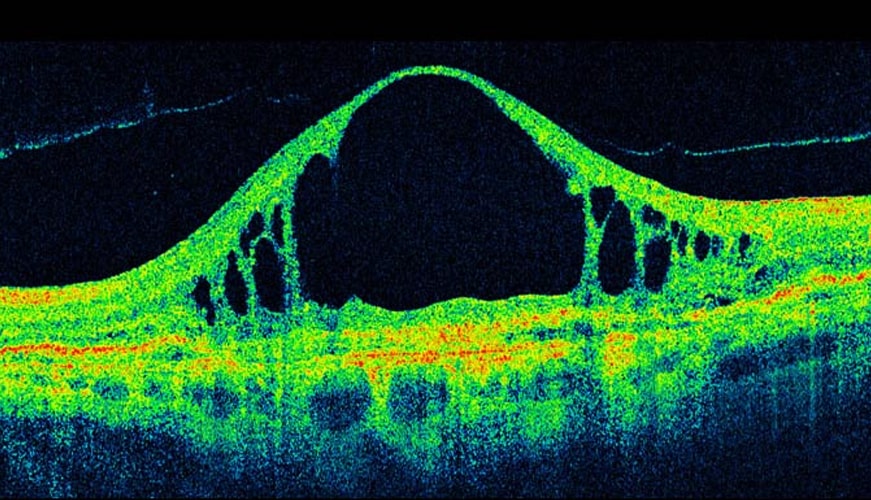

OCT Scanning

At R. A. Glass, we are passionate about eye health. As part of our commitment to provide you with the very highest standard of eye care, we have invested in cutting-edge Optical Coherence Tomography (OCT) technology which allows us to examine the back of your eyes in exceptional detail.